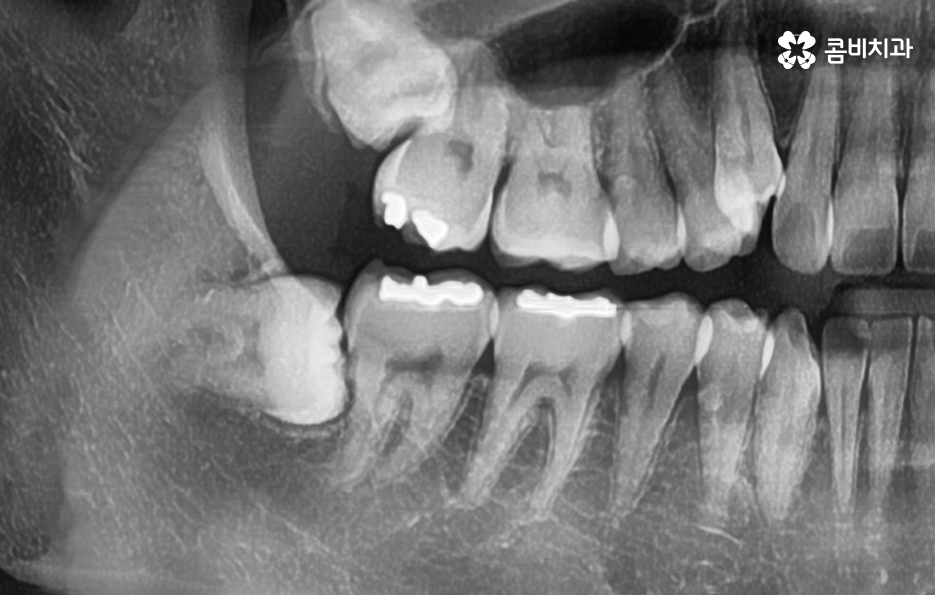

저작 기능에서 주된 역할도 하지만 위 사진을 다시 보시면 사랑니가 부분 매복되어 있는 상태로 누워서 자라고 있기 때문에 사랑니와 어금니 인접면에서 청결 관리가 잘 안되는 문제로 충치나 치주질환을 앓고 계신 분들도 많기 때문에 사랑니로 인해 어금니 문제가 발생하는 경우도 많이 있어요

다시 위 어금니 사진을 살펴보면 사랑니가 매복되어 있긴 하지만 위쪽 부분이 살짝 잇몸 밖으로 드러나 있는 것을 볼 수 있는데요. 평소 칫솔질을 잘하더라도 사랑니로 인해 청결관리에 미흡한 점이 생기면 주변 치아에도 충치가 전염되는 등의 안좋은 영향을 주는 경우가 많으며 부분 매복 사랑니의 경우 충치가 아니더라도 잇몸 염증의 주된 원인이 되고 있기 때문에 발치하는 것을 각종 구강질환을 예방하기 위해 권하고 있어요

오늘 케이스 사진의 경우 사실상 사랑니 하나만 보더라도 주변 치아에 충치 및 치주질환을 일으키기 쉬운 사례이며 누운 사랑니로 인해서 어금니의 씹는면 만이 아니라 인접면 충치나 손상으로 이어지기 사례로도 볼 수 있는데요